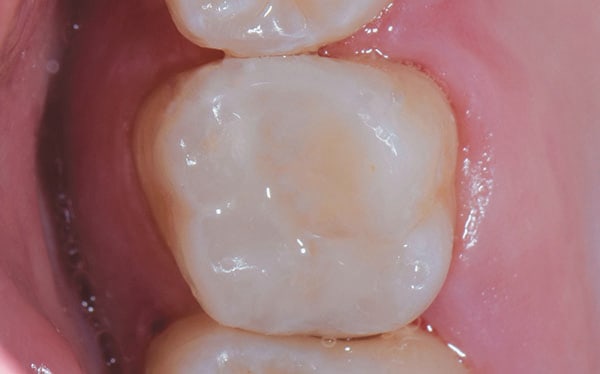

A 22-year-old patient presented for a re-care examination during which a preexisting occlusal composite restoration on tooth No. 14 was found to be undermined and fractured. It was not clear how long ago the composite had been placed. Although caries was clinically evident marginally and on the mesial aspect of the tooth (Figure 1), the patient did not report experiencing any sensitivity associated with the tooth or that area of the dentition. The patient was advised of the issue, shown the area of decay, and agreed to re-treatment with a Class II composite restoration.